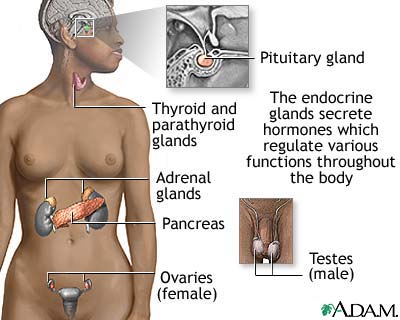

Pheochromocytoma is a rare tumor of adrenal gland tissue that typically arises from the adrenal gland. It results in the release of too much epinephrine and norepinephrine, which are hormones that control heart rate, metabolism, and blood pressure.

Pheochromocytoma may occur as a single tumor or as more than one growth. It usually develops in the center (medulla) of one or both adrenal glands. The adrenal glands are two triangle-shaped glands. One gland is located on top of each kidney. In rare cases, a pheochromocytoma occurs outside the adrenal gland. When it does, it is usually somewhere else in the abdomen.

Adrenal glands